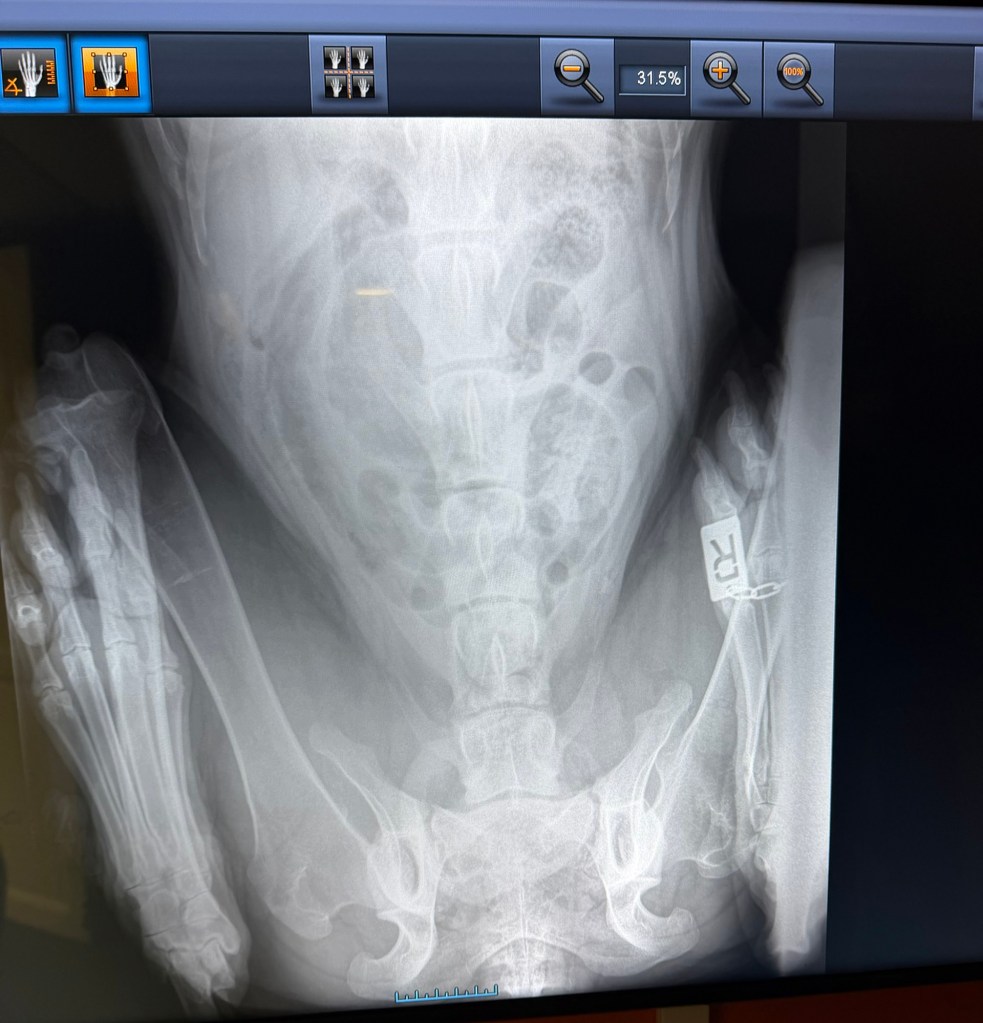

Freki har også vært på røntgen nå i november 2025, i en alder av 3år og 8måneder. Dette grunnet et ønske om å avdekke eventuelle svakheter eller forandringer i skjelett. Freki er en kraftig og stor hund med mye muskler og kraft, så her er det store påkjenninger. Rygg og albuer ble sjekket og resultatene var fantastiske og meget bra! Han har mikroskopiske forandringer i rygg og en flott bakpart med robust lende-rygg. Albuene er som tidligere, uten stor signifikant forandring. En frisk og sunn 4 åring! Freki har et utrolig flott vesen og er en ordentlig glad Bamse-gutt med masse kjærlighet til alle.